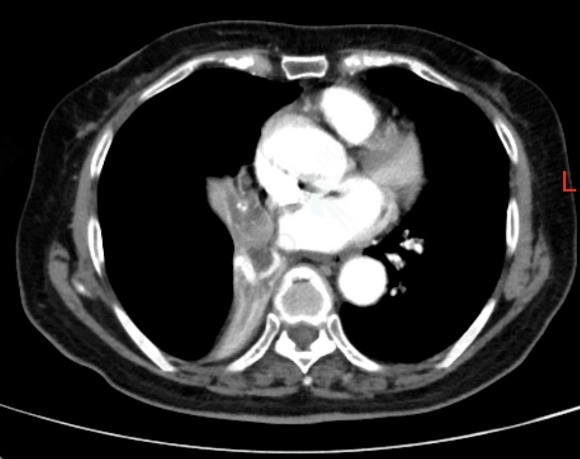

夏奶奶近两年来一直被间断的胸闷、气短、咳嗽、咳痰困扰。半月前,她的病情急剧加重,出现了痰中带血的症状,家人紧急送至东院区。呼吸与危重症医学科阎杰副主任医师接诊后,立即为夏奶奶进行胸部增强CT检查。结果提示“右肺门增大,右肺主支气管内结节状软组织密度灶,右肺下叶不张”,高度怀疑恶性肿瘤。

患者CT检查